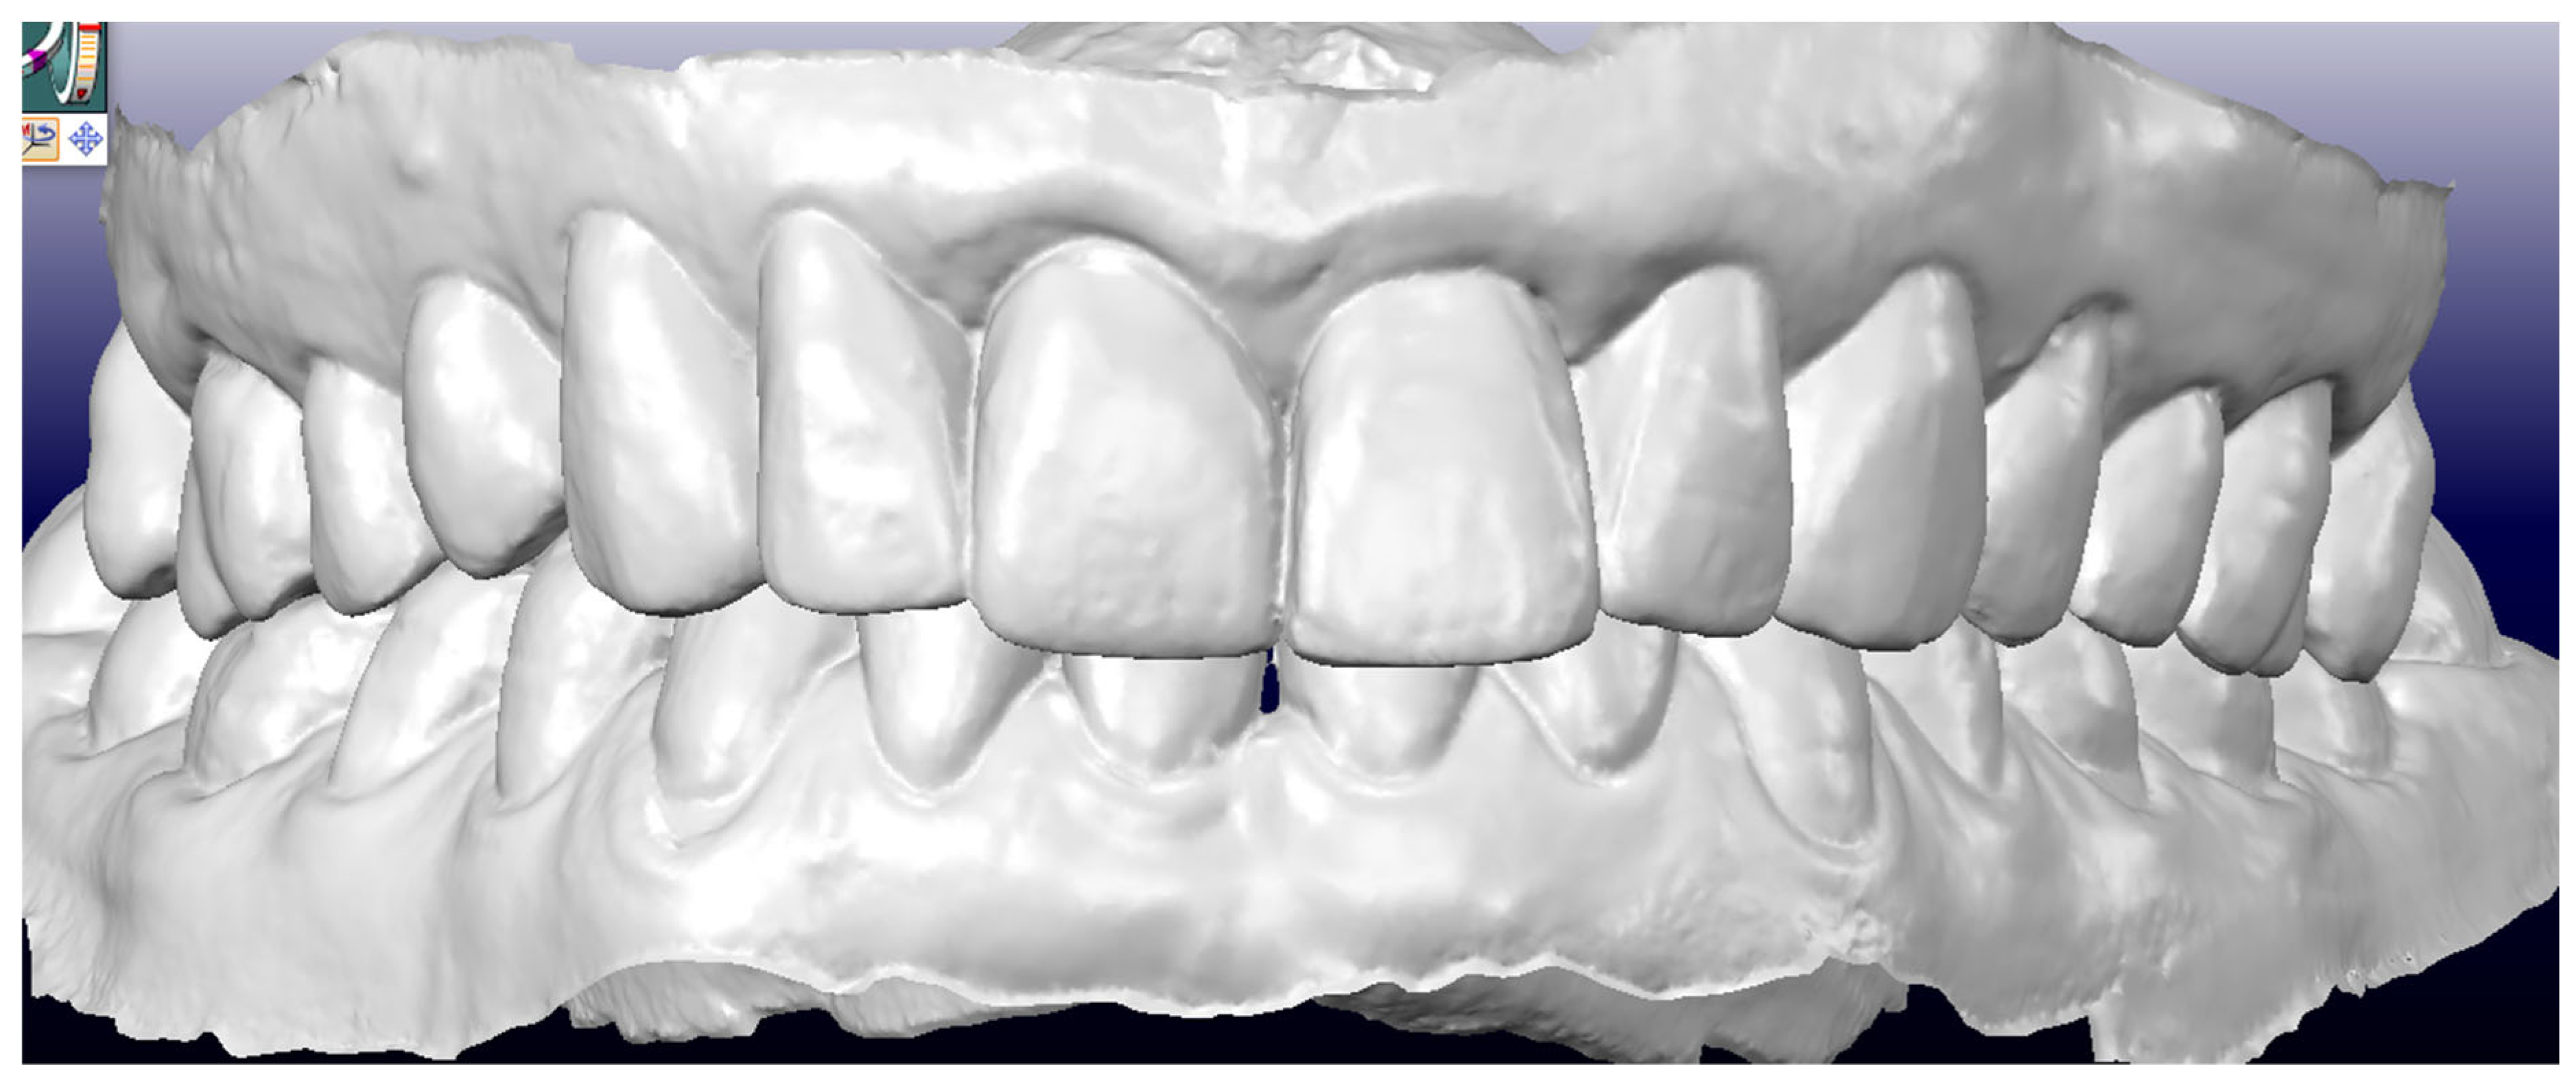

A three-dimensional iTero scan (iTero Element, Align Technology, San Jose, CA, USA), extraoral and intraoral photos using the dedicated application Invisalign Practice App (Align Technology, San Jose, CA, USA) as well as a pantomogram were taken during the visit.

- Pretreatment occlusion scan using the iTeroTM 5.0 scanner, extracted into OrthoCAD 5.9.1.50 software (Align Technology, San Jose, CA, USA) (Figure 4), extra- and intraoral images taken with the Invisalign Practice App (Align Technology, San Jose, CA, USA) and pantomogram (Figure 5). Based on the iTeroTM 3D scan (Align Technology, San Jose, CA, USA) and occlusal examination, it was decided to use the Invisalign® system (Align Technology, San Jose, CA, USA) with the Express 1 arch subtype—the shortest possible treatment with seven aligners (and seven additional aligners) involving only the upper arch because the aim was to eliminate the occlusal injury of one tooth by its intrusion and a change of the anterior–posterior and mesiodistal inclination. The first treatment plan was performed using the ClinCheck 6.0 software (Align Technology, San Jose, CA, USA), which assumed movements of tooth 21—the main movement was a palatal inclination of the crown by 4.4 degrees, a distortion by 3.3 degrees and an intrusion by 0.4 mm (Figure 6). The analysis of this plan showed that it was impossible to eliminate the traumatic occlusion when changing the position of only one tooth in the arch (Figure 7)—the analysis showed numerous abnormal occlusal contacts.

Figure 4. Pretreatment occlusion scan performed using the iTeroTM 5.0 scanner, extracted into OrthoCAD 5.9.1.50 software: extraoral and intraoral images.

Figure 5. Pantomogram—visible porcelain restorations and an implant in area 14.